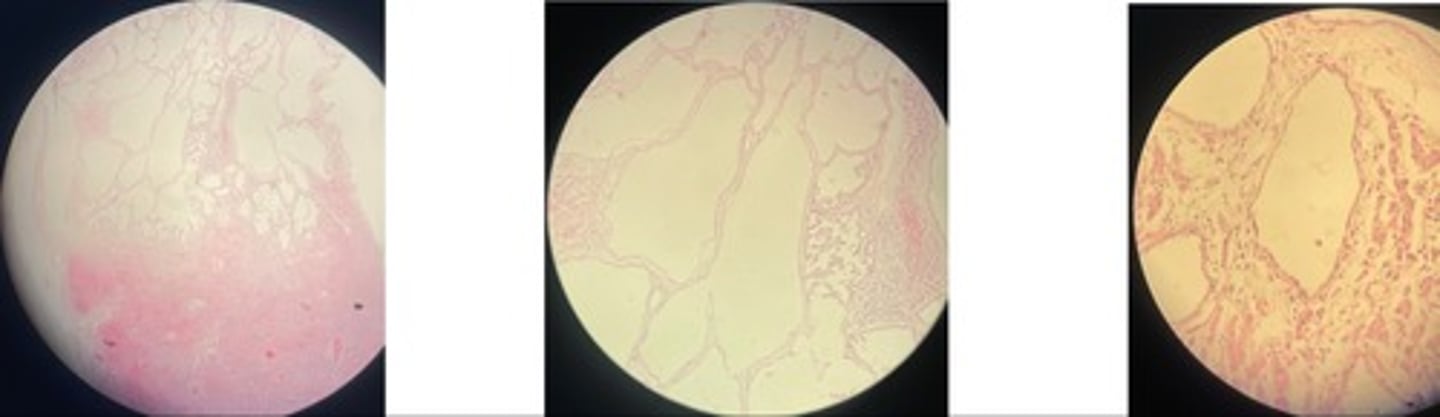

Chronic interstitial pneumonia

- thickened alveolar septa …narrowed lumen

- lymphoid follicles around bvs

- prolif of s.m cells

Parasitic pneumonia

- distended alveoli, bronchi + bronchioles

- degenerated + mononuclear cells

- s.m + epi hyperplasia … thickened alveolar septa

- exudate + emphysema … congestion